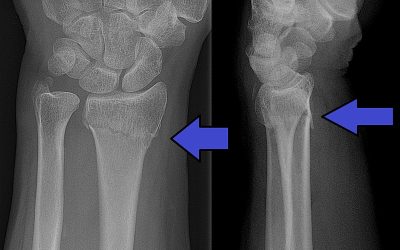

Fractura de Colles: Una lesión común en la muñeca

Introducción:La fractura de Colles es una lesión ósea común que afecta la muñeca. Recibe su nombre en honor al cirujano irlandés Abraham Colles, quien describió por primera vez esta lesión en el siglo XIX. Esta fractura ocurre en el extremo distal del radio, uno de...